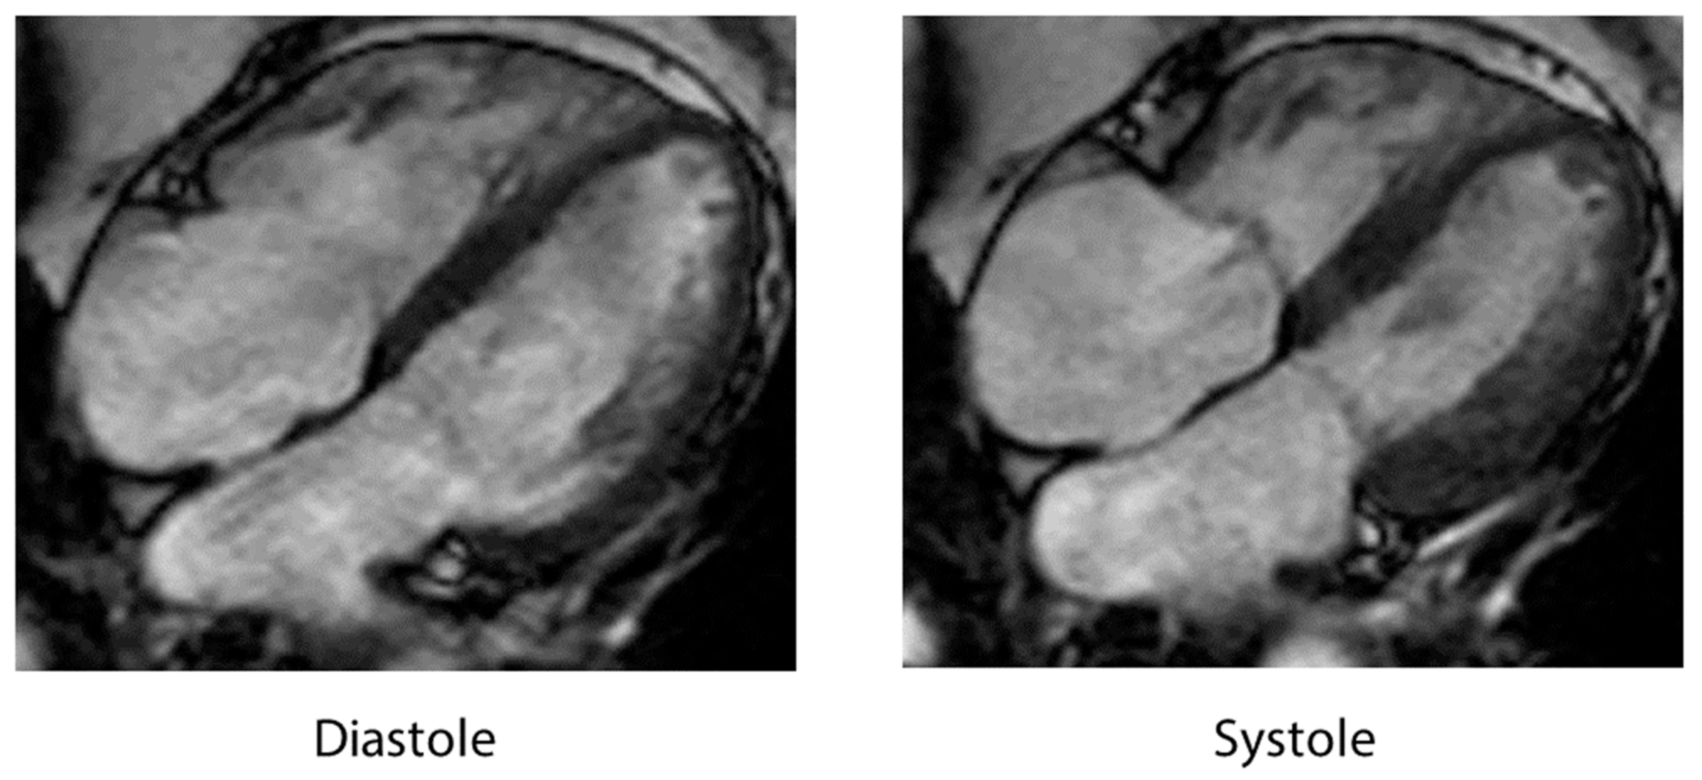

4.5. Cardiac Magnetic Resonance Imaging

| CMR (cardiac magnetic resonance) | RWMAs, RV involvement, late gadolinium-enhancement signal intensity threshold < 5 SD, and edema using T2 weighted imaging in dysfunctional LV regions. |